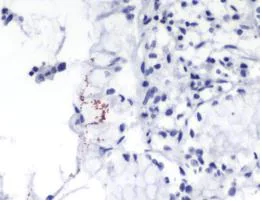

Immunohistochemistry (Formalin/PFA-fixed paraffin-embedded sections) - Anti-Helicobacter pylori antibody [SPM526] (AB231433)

Formalin-fixed, paraffin-embedded human H. pylori-infected stomach tissue stained for Helicobacter pylori using ab231433 at 1/100 dilution in immunohistochemical analysis.